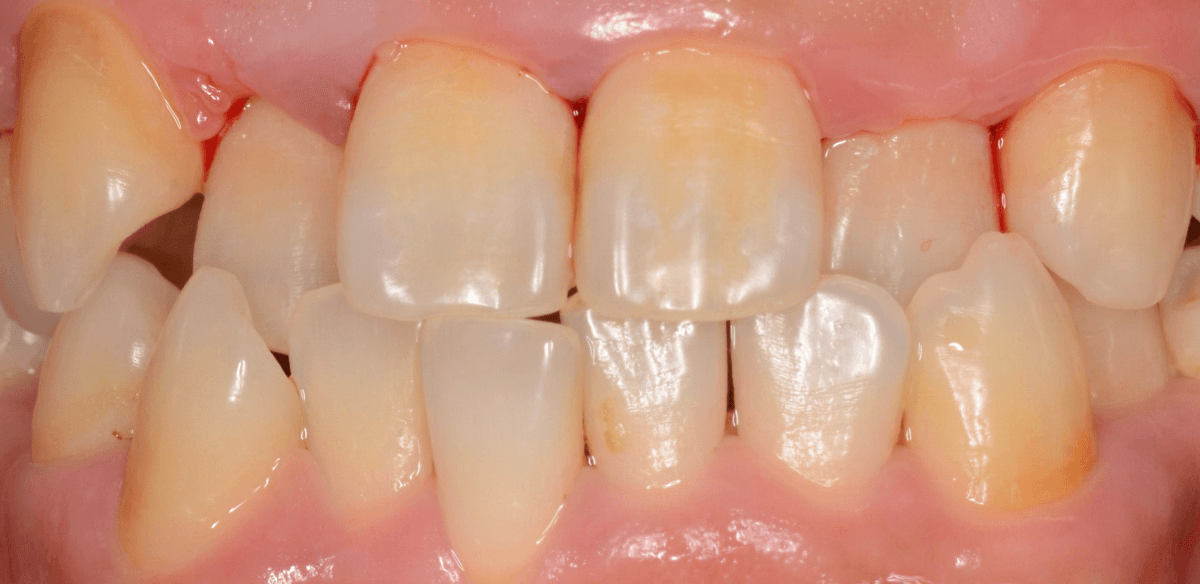

Case.2

今回は、上の前歯の縁下歯石の除去をしたお話です。

写真の左の矢印の歯肉が退縮して腫れています。

右の矢印の歯肉と比べてみるとわかると思います。

こういった歯肉の形をしている部分は、歯石がたまっていることが多いです。

拡大してみると、縁下歯石(歯肉の中に入り込んだ歯石:歯肉に大きく悪影響を与えます)が顔を出しているのがわかります。

かなり歯肉の中に歯石が入り込んでしまっていると思われます。

歯肉の中の歯石は歯にべっとりとこびりつきますので、除去するには麻酔をして引きはがす処置が必要です。

歯石除去後、約1週間です。

歯肉がひきしまってきたのがわかるでしょうか。

治療前との比較です。

比べると、違いがわかると思います。

まだ若い患者さんで本格的な歯周病に進行する前ですので、歯ブラシの徹底によって、もっと歯肉が改善されるのも期待できます。

逆に、歯周病が本格的に進行してしまうと、歯石除去をしても歯肉や歯の周りの骨は完全には元には戻りません(><)

その後、この患者さんは熱心に通院とお手入れをされて、約二か月が経ちました。

歯肉は順調に引き締まってきました。

歯周治療は、ご本人のメンテナンスなしには結果が出ません、頑張ってらっしゃる形が見えて、とても嬉しいですね

こちらが比較写真です。

並べてみると、治り具合がよりわかりますね